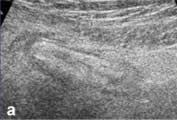

| а, г - продольное и поперечное сканирование (соответственно)

визуализируемого фрагмента червеобразного отростка в В-режиме.

Последний определяется в виде слоистой структуры цилиндрической

формы до 10 мм в диаметре. |

б, д - продольное и поперечное сканирование

(соответственно) визуализируемого фрагмента червеобразного

отростка в режиме дуплексного допплеровского сканирования.

Прослеживается сосудистый рисунок в стенке отростка. |